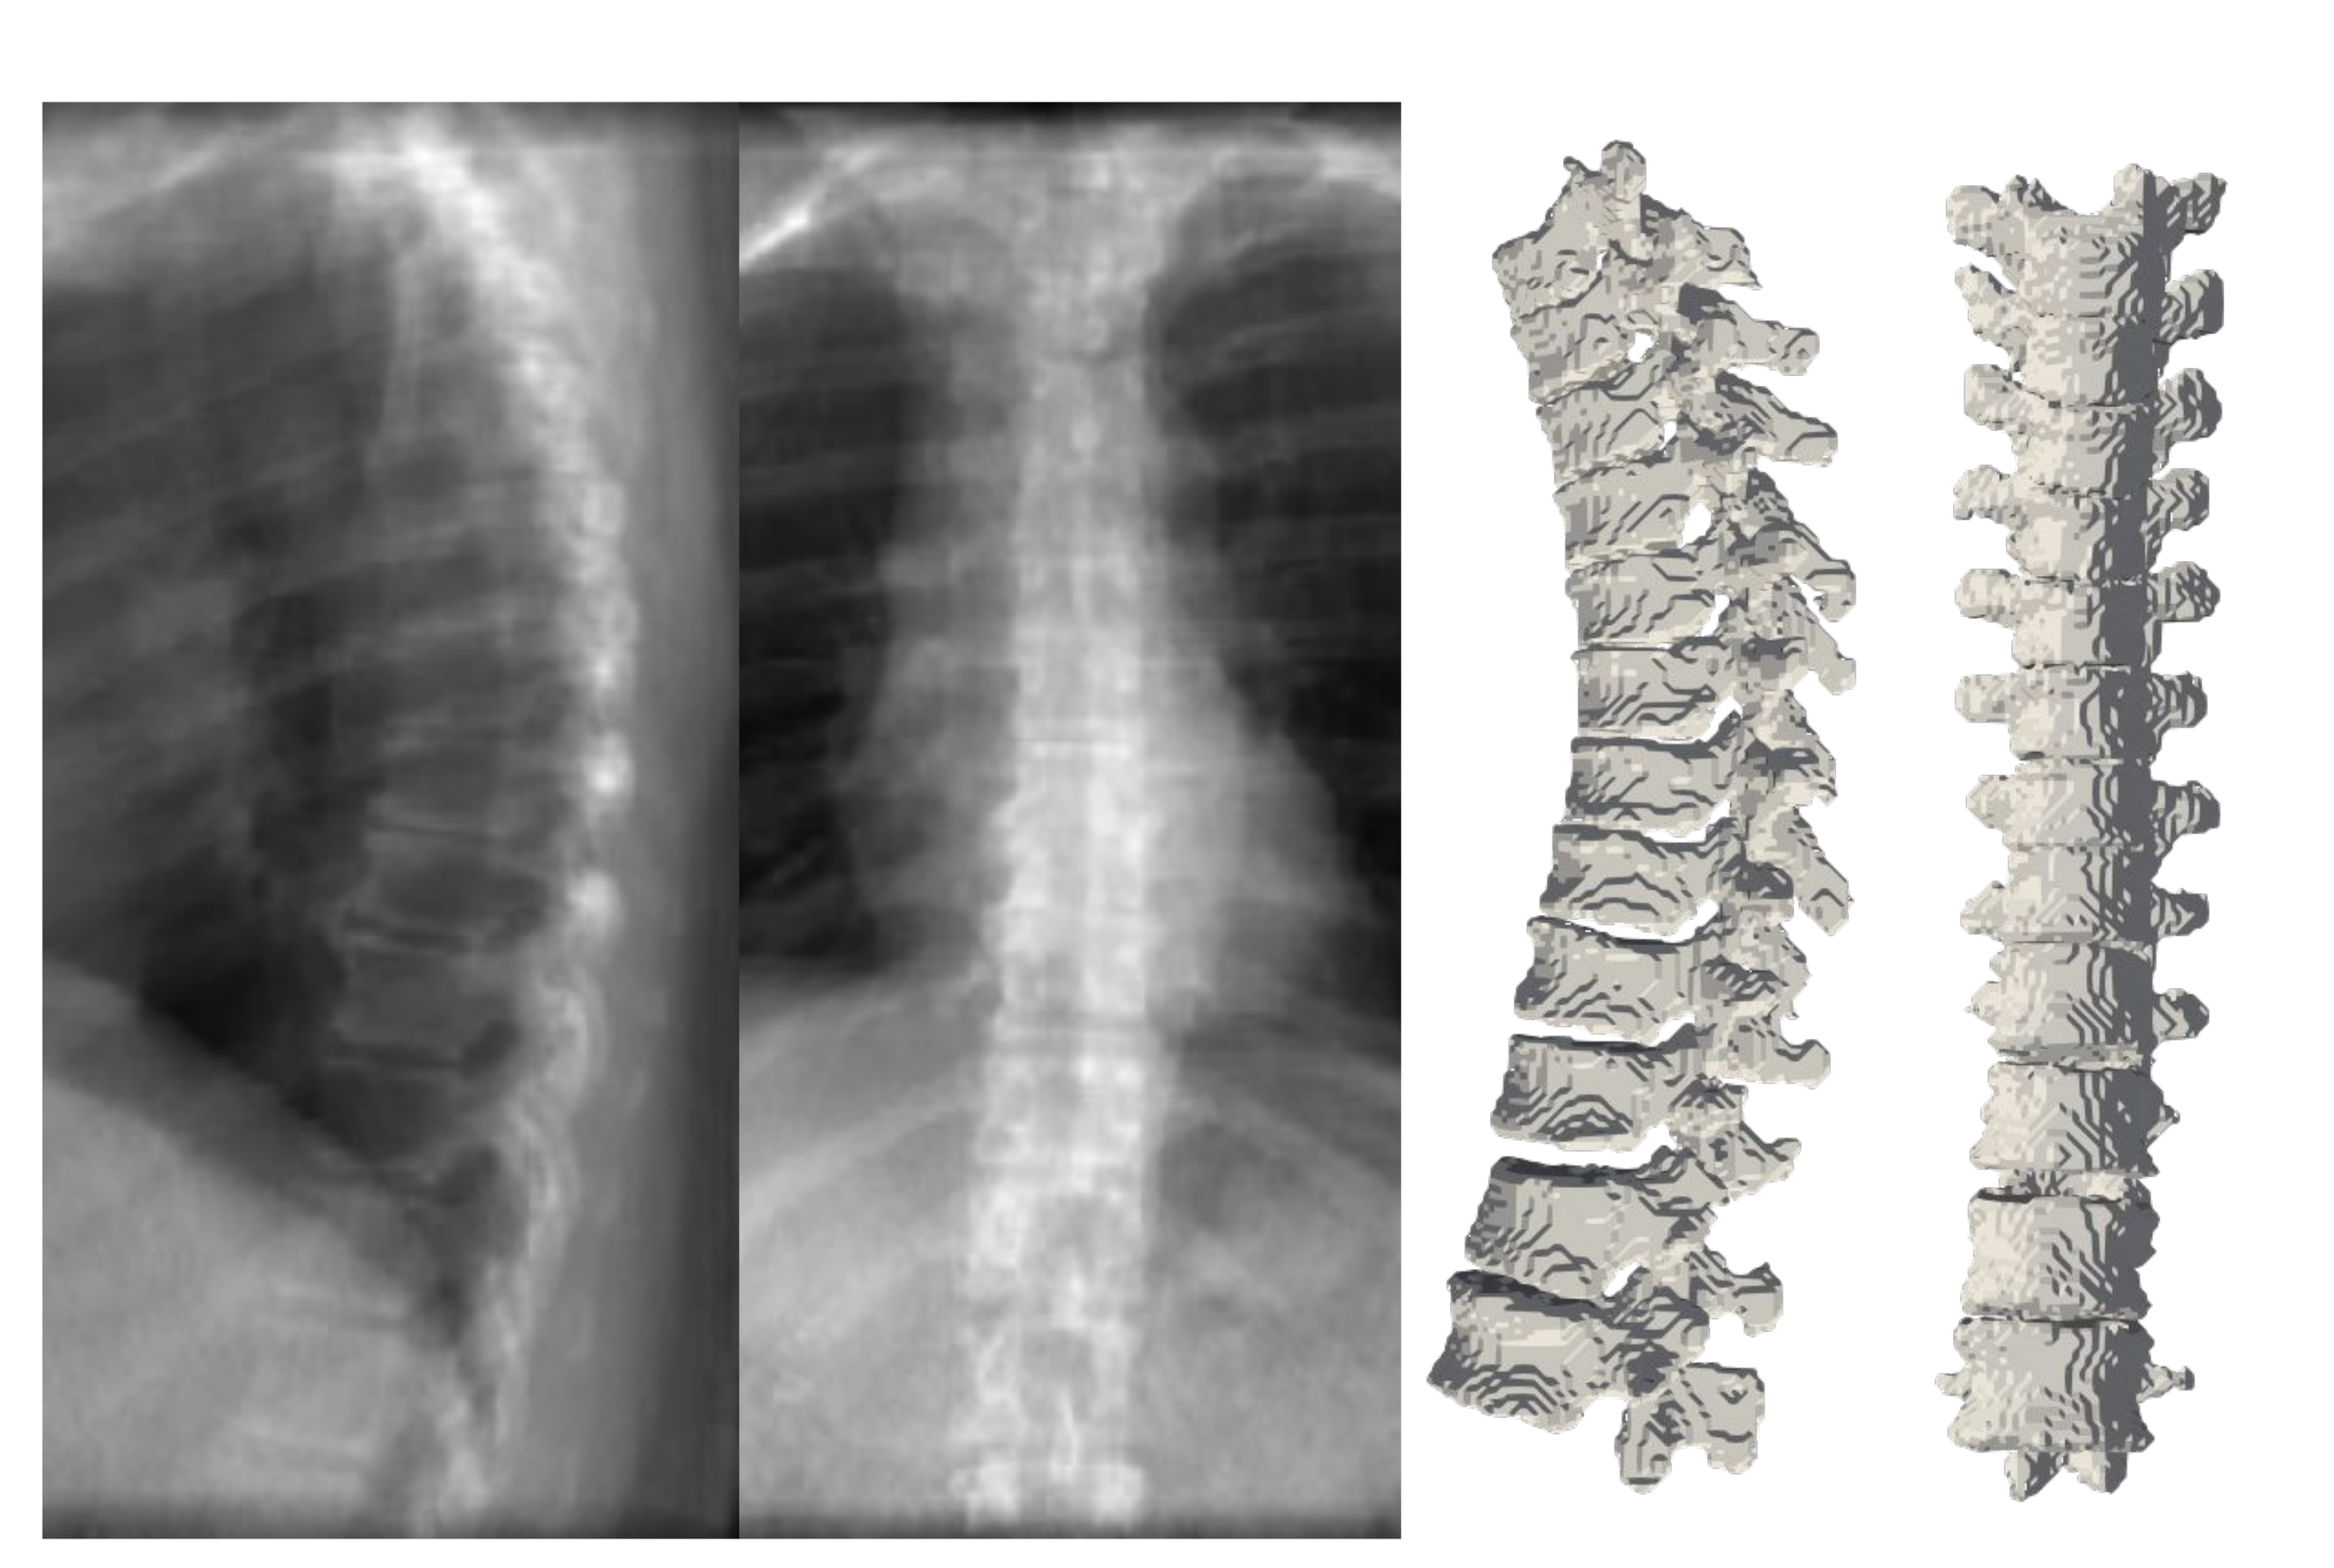

Figure 10 depicts the results of deploying TransVert+ for reconstructing the 3D, patient-specific posture of the upright standing spine. As stated, there is no 3D ground truth spinal model for the clinical radiographs. Observe the matched reconstruction of the 3D spine posture to the spinal posture in radiographs.

Figure 10. Full 3D spine models: 3D patient-specific spine models constructed from real clinical radiographs. Each sagittal and coronal view radiograph pair is from a different patient.